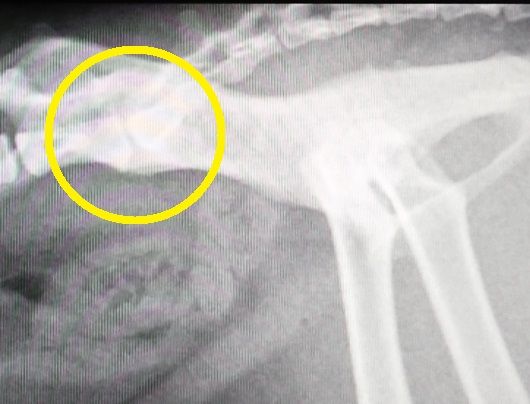

2016年:11歳のレントゲン

背骨と尻尾の付け根の骨の状態の経過を年を追って見てみると、若い頃は、骨と骨の隙間もしっかり開いてましたが、2015年のレントゲンでは、先ずは、隙間がかなり狭くなって来ており、更に、2016年のレントゲンでは、骨の下の部分に突起が、これを我が家ではトケトケと呼んでいます。

本日のレントゲンでは、隙間が無くなり、トケトケもかなり飛び出て来ています。

人間であれば、外科手術で痛みを除去する方法も有りますが、動物の場合は、それも難しく、何とか少しでも痛みを緩和する方法を模索していく事になりそうです。